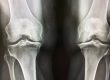

“Arthritis” simply means joint inflammation. Joints are areas in which two bones meet, like your fingers or elbows.

Typical symptoms of arthritis include inflammation, redness, pain, and heat throughout your joints.

- Osteoarthritis is the most general type of arthritis and is more common in older people.